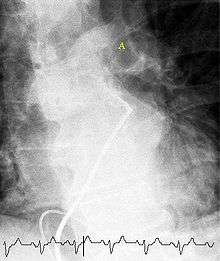

(A) After inhalation of 20 mCi of Xenon-133 gas, scintigraphic images were obtained in the posterior projection, showing uniform ventilation to lungs.

(B) After intravenous injection of 4 mCi of Technetium-99m-labeled albumin, scintigraphic images shown here in the posterior projection. This and other views showed decreased activity in multiple regions.